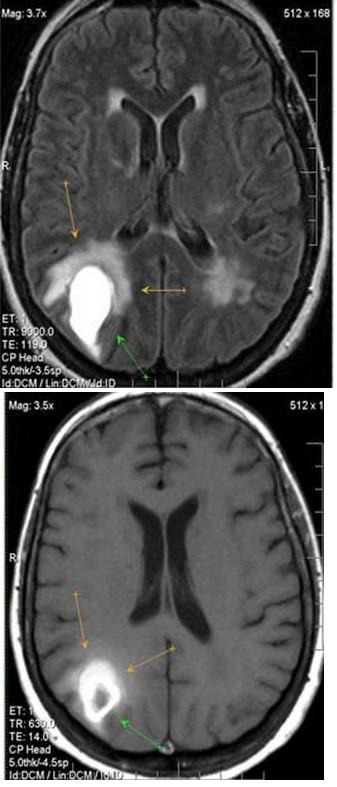

|

| Геморрагический инсульт на МРТ головного мозга |